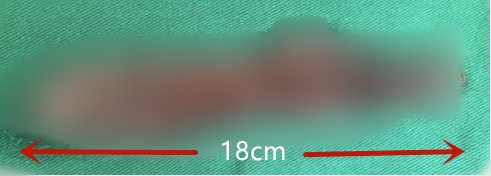

来院时,明明已经进食困难,胳膊也没有力气,走路需要靠家人搀扶。“肿瘤上至高颈髓,下到胸椎第2节,长度达到了18公分,”王贵怀说,“此前,肿瘤已经出血,对脊髓造成了更大的损伤。同时增加了手术分离难度,因为出血后不仅肿瘤边界更加模糊,而且肿瘤与脊髓更加黏连。另外,瘤体还有二次出血的风险,若不及时手术,很可能会造成截瘫甚至危及生命。”

切除的瘤体